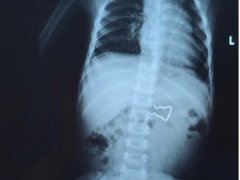

Bé 18 tháng tuổi nuốt móc sắt vào ruột, cha mẹ hốt hoảng đưa đi cấp cứu

Kết quả chụp X-quang cho thấy dị trong ruột bệnh nhi là vật dùng để cố định trong kẹp quần áo, có 2 cạnh sắc nhọn với kích thước lớn.